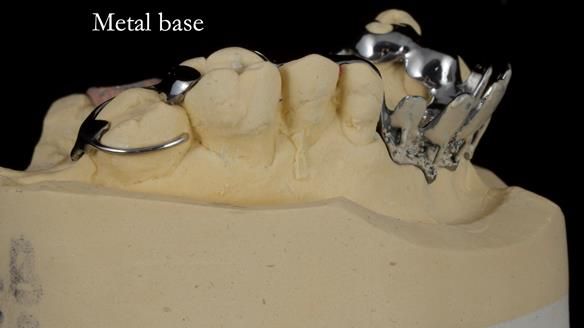

1. Denture design: A custom cobalt-chromium framework was Scandinavian-designed to maximise stability, protect the remaining teeth, and allow for future additions if needed.

Keith’s denture incorporated a Duracetal shell clasp on upper right first premolar (Myerson), which are designed to be virtually visible, providing a more aesthetic solution while enhancing patient comfort. The Scandinavian-inspired approach, based in modern removable prosthodontic techniques, ensured the denture was not only durable but also visually pleasing. Additionally, the design was carefully planned to allow for future modifications, ensuring that if Keith loses additional teeth, the denture can be adapted rather than replaced entirely.